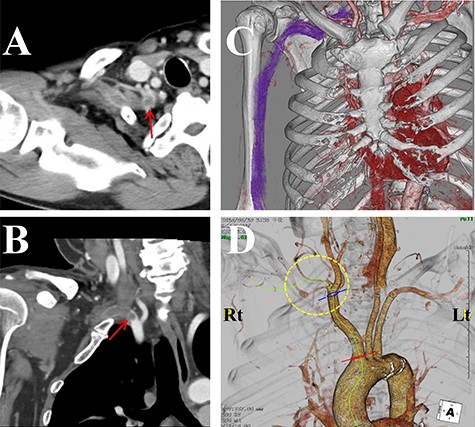

The laboratory data revealed inflammation (white blood cell: 17 500/μl; C-reactive protein: 19.34 mg/dl). Although an increase in D-dimer levels (1.1 ng/ml) was not observed, the contrast-enhanced CT imaging revealed that the subclavian artery was occluded, and a successive distal arterial embolism was produced (Fig. 4). We diagnosed him with an acute arterial occlusion associated with TOS.

Contrast-enhanced computed tomography (CT) images of the thorax. (A) Axial view. (B) Coronal view. (C, D) Three-dimensional CT images. The subclavian artery (circle) was occluded due to a thrombus (arrow) at the level of the dysplasia of ribs.